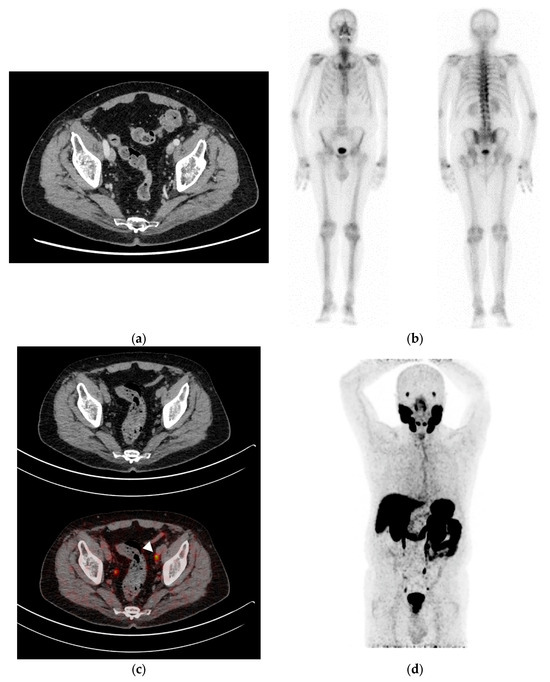

3.4. Comparative Performance of Bone Scintigraphy and PSMA-PET/CT

3.5. Comparative Performance of PSMA-PET/CT and Conventional Imaging

3.6. PSMA-PET/CT Accuracy in Pelvic Lymph Node Staging